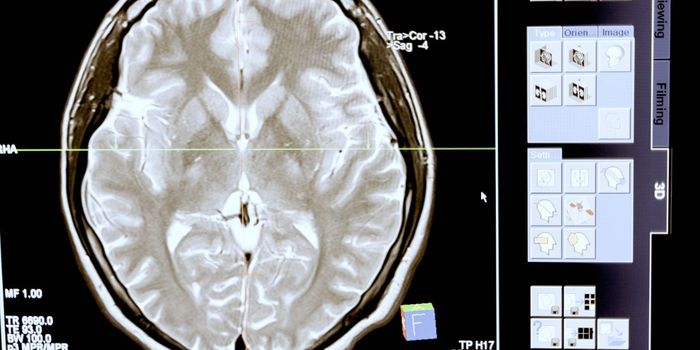

MAR 05, 2024NeuroscienceCan we map the brain to show its behavior patterns when a patient is healthy and sick? This is what a recent study publi ...